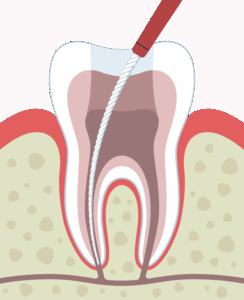

感染した虫歯部分を丁寧に削る

感染している歯髄や膿の除去

薬剤を使用して洗浄・消毒

細い針を用いて神経を除去していきます。